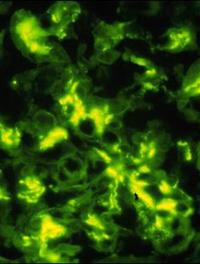

Sous le terme d’amylose on regroupe des maladies caractérisées par des dépôts extracellulaires de protéines insolubles sous forme de [...]